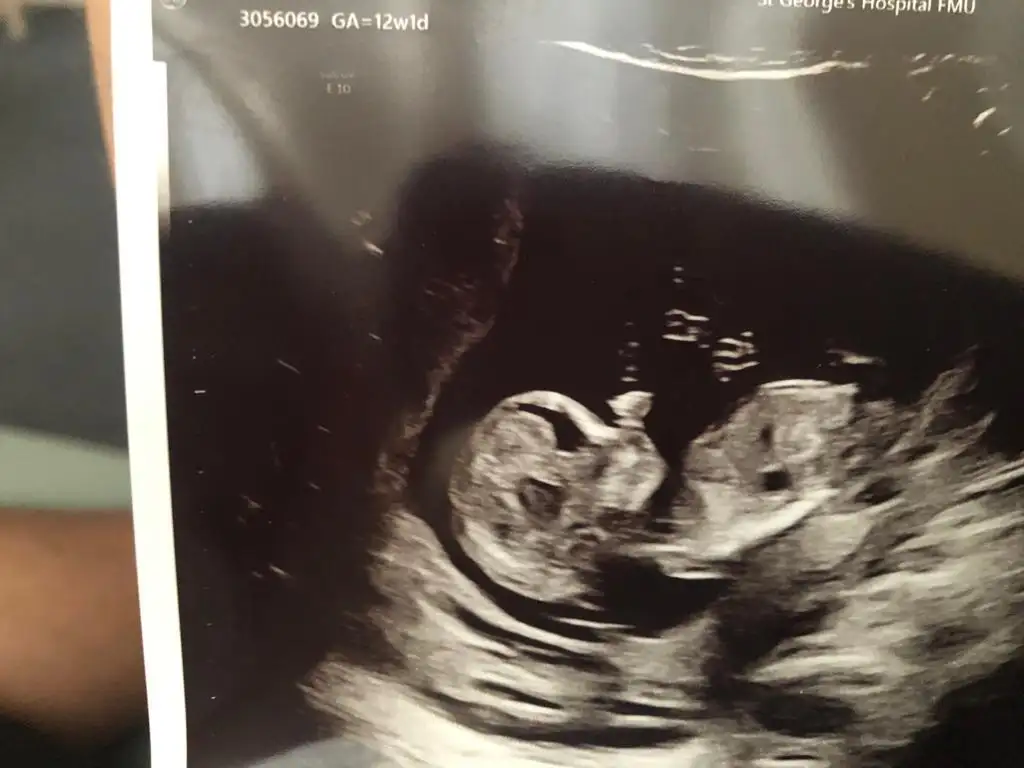

dr soylemeden siz gorun genital nub teorisi ( bebegin cinsiyeti)

13+5 ultrason görüntüsü, bizi de tahmin eder misiniz :)